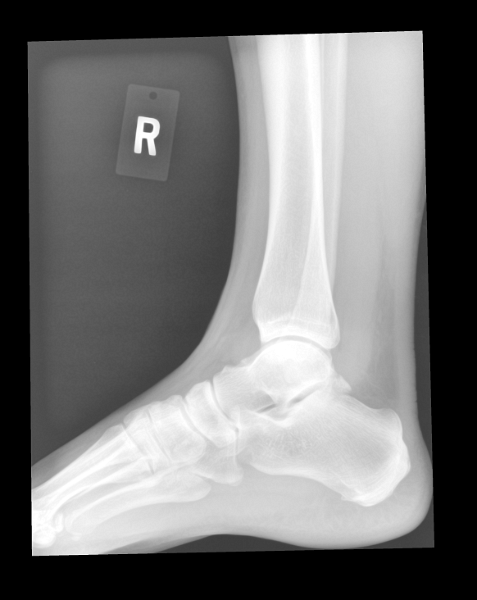

Ankle (1) Ankle (1) Ankle (2) Ankle (2) Ankle (3) Ankle (3)

Ankle (4) Ankle (4) Ankle (5)